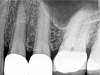

Figure 7 shows another tooth that was diagnosed with a necrotic pulp; Figure 8 shows a preoperative CBCT slice from the volumetric scan of the tooth. The clinician observed that there was more than one canal in the mesiobuccal system and that a periapical lesion was present. Lesions were visible radiographically on every root, adjacent to numerous portals of exit in the apical one-third. In this case, the clinician aimed to be more conservative and was able to better maintain the original anatomy. In the mesiobuccal root, the canals crisscrossed, and considering the delicate anatomy in the apical one-third, it was imperative to keep the foramen as small as practical. A much larger palatal canal was also observed. The clinician provided a coronal seal buildup before the rubber dam was removed from the tooth. Figure 9 shows the postoperative 2D radiograph.

Fig 7. Preoperative radiographic image (Fig 7), preoperative CBCT (Fig 8), and postoperative radiographic image (Fig 9).

Figure 7

Fig 8. Preoperative radiographic image (Fig 7), preoperative CBCT (Fig 8), and postoperative radiographic image (Fig 9).

Figure 8

Fig 9. Preoperative radiographic image (Fig 7), preoperative CBCT (Fig 8), and postoperative radiographic image (Fig 9).

Figure 9